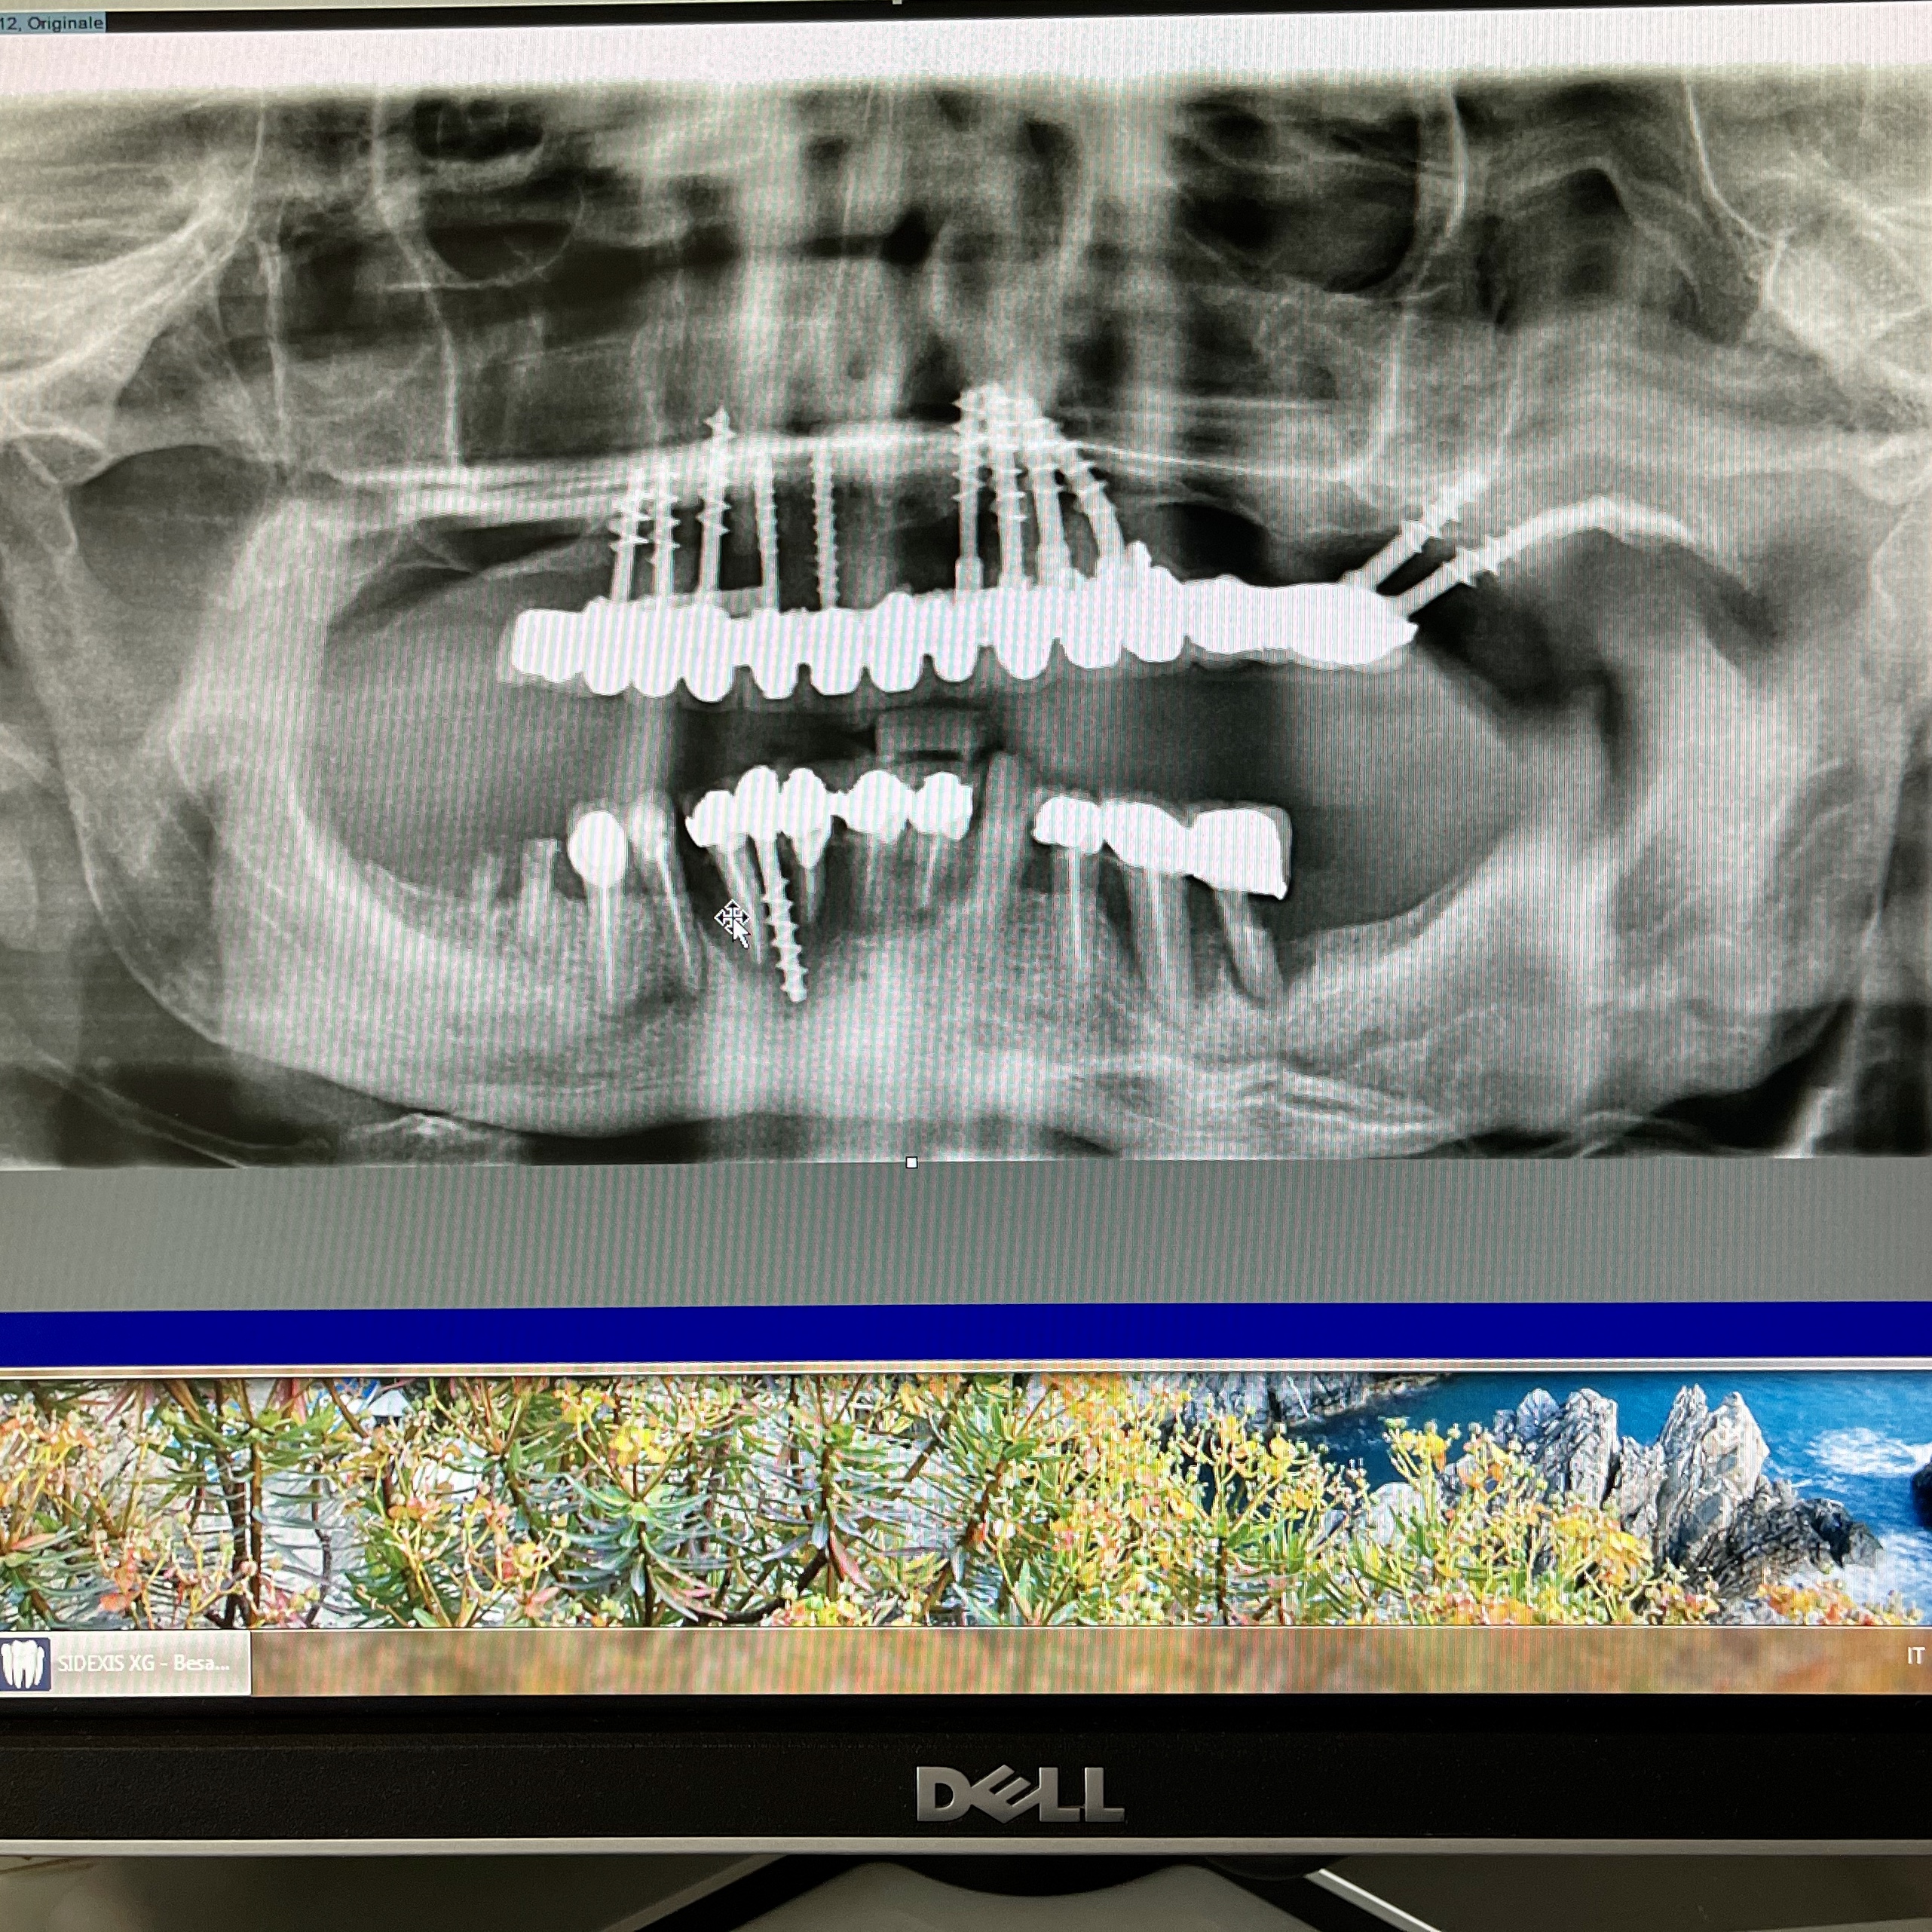

6 - COMPARISON BETWEEN OSSEOINTEGRATED IMPLANTOLOGY AND ITALIAN SCHOOL IMPLANTOLOGY

CONSEQUENCES OF THE DIFFERENT OPERATION BETWEEN THE TWO METHODS: During the design, during insertion, during healing and after healing.